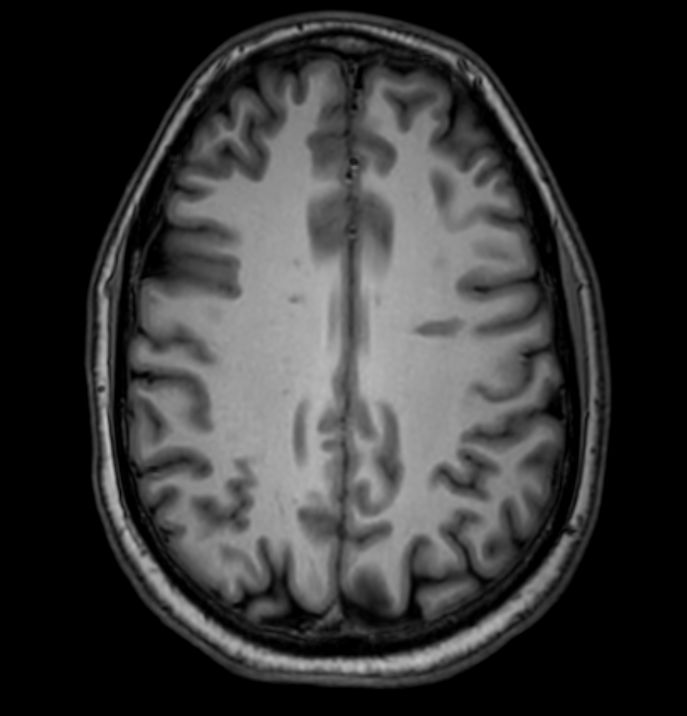

3D VIEW - T1w TSE (axial reformat)

Pre-Gado

Axial 3D VIEW - T1w TSE

Post-Gado